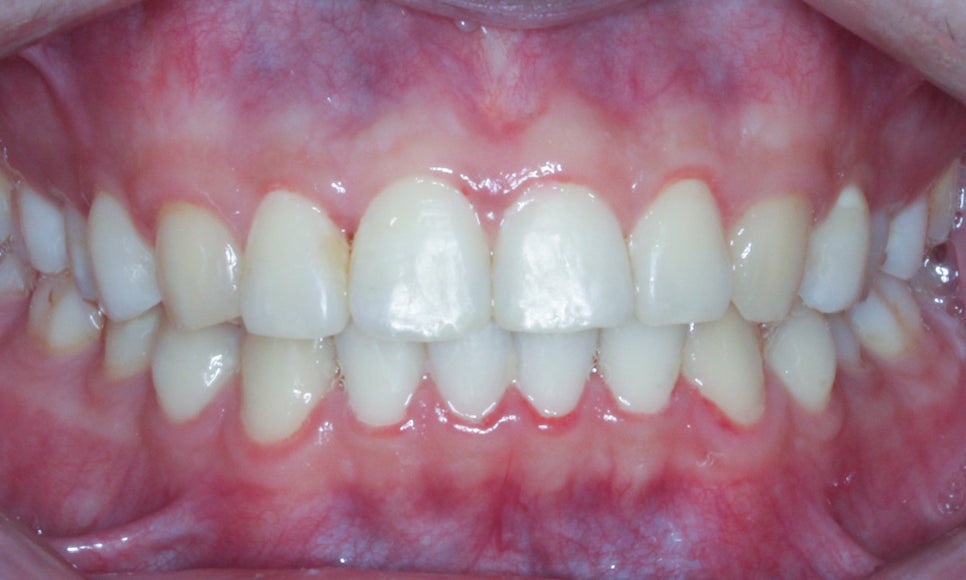

상악과 하악의 안쪽면 역시

가지런하게 배열된 모습이네요

특히 치아 크라우딩이 발견되었던

하악의 전치부가 예쁘게 정돈된 모습이죠?

이번 환자분께서는 빠른 효과의 심미치료가 아닌

교정치료로 자연치아를 살리고 싶어하셨기에

약 15개월의 교정 기간이 소요되었습니다.